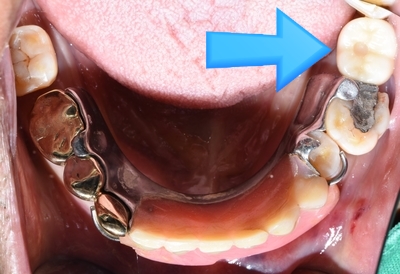

먼저 환자분이 위 사진에서 손가락으로 가리키는 부분 어금니를 아파하셔서 발치하셔서 비어있는 사진이고요,

일단 환자분이 임플란트 수술은 너무너무 무서워 하셔서 위 틀니만 제작하였습니다.

연세예감치과에서 어금니 네비게이션 임플란트 완성 후 사진 ▼

![[종로/시청역]실제 환자의 보험 임플란트, 보험 틀니 사례 소개합니다. 젊어지는틀니,임플란트 치료 관련 이미지 7](https://pub-9f2bb3498faf4d1d8714b41df24753e3.r2.dev/content/clinics/archive/rseeanjxfu/naver_blog/yonseiyegam/assets/by_hash/cad4cf09ba92d890f1fcec2d0a3a69c58f0cb68bf0993c276ee83319ed5c1147.jpg)

요렇게 화살표가 가리키는 부분에 네비게이션 임플란트가 들어가게 되었습니다.

임플란트 수술을 하시고 나서는 "하나도 안아파서 임플란트 수술 한것 같지도 않다"라는 소감을 전해주셨습니다.